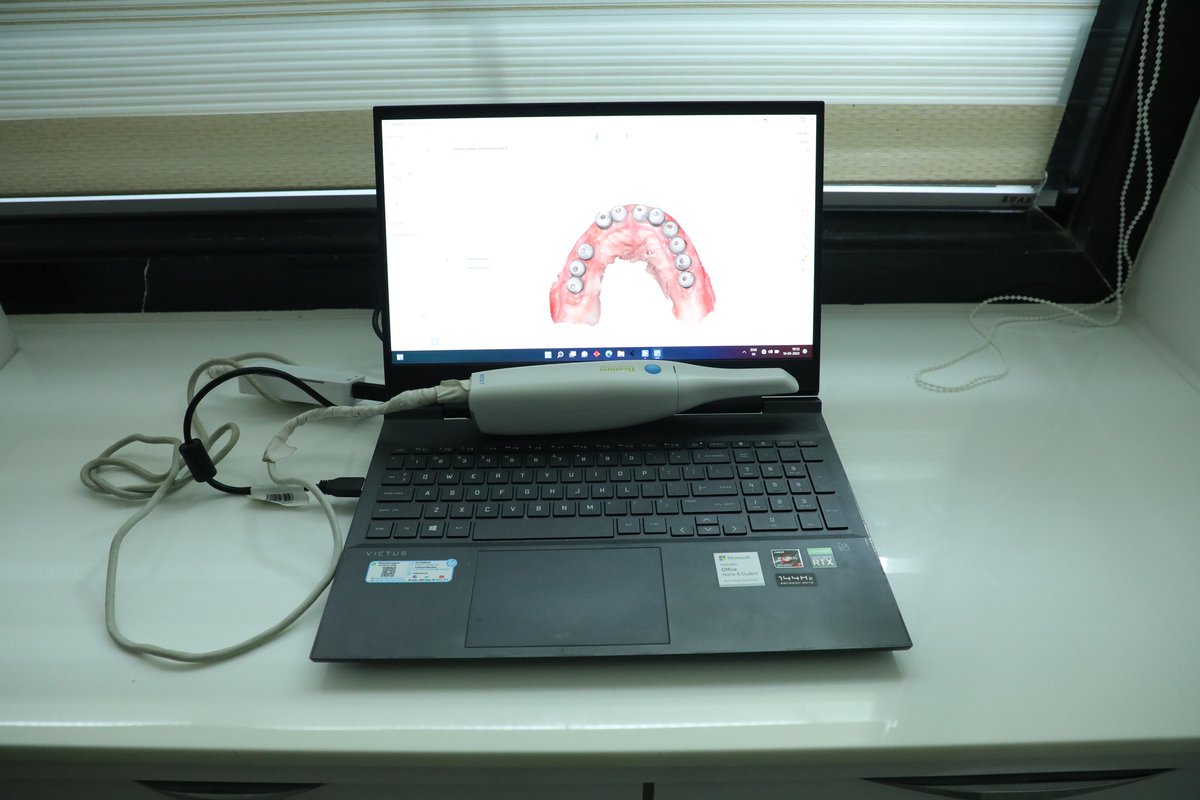

حول عيادة الدكتور ريتشا كوزمودنت لمستحضرات التجميل والأسنان الدكتور سوابنيل باندي والدكتور. ريتشا ميهتا هي المؤسس المشارك للدكتور ريتشا Cosmodent. وقد أكمل كلاهما برامج MDS في زراعة الأسنان ، والتيجان ، والأسنان.. Swapnil عملت أيضا نحو دكتوراه. في زراعة الأسنان. عيادة الأسنان المعتمدة من قبل ISO هي Dr. منشأة Cosmodent في Richa. مع رضا المريض بنسبة 100 ٪ ، نحن نتمسك بمعايير عالمية صارمة في التعقيم والنظافة والرعاية الجيدة وإدارة الممارسة. واحدة من... (عرض المزيد)